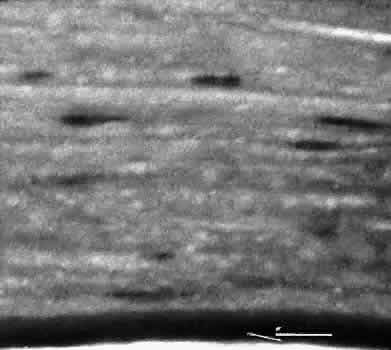

Fig. 5. Collagen lamellae retract when cut, causing the wound to gape when incised. If the extent of the incision is limited, as in clear cornea cataract incisions, the gaping may be countered by swelling of corneal stroma exposed to aqueous media. (Hematoxylin-eosin stain; × 100.)

Fig. 6. Descemet's membrane (D) has elastic properties that cause inward curling when incised. The fibrous reaction between cut ends of Descemet's membrane indicate a wound of long standing. (PD stain; × 100.)